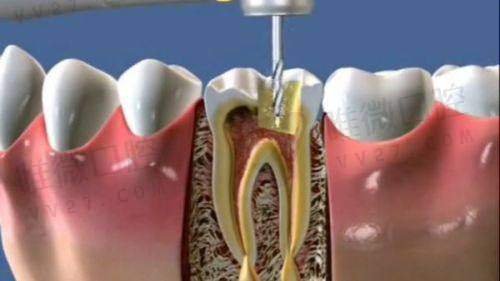

根管治疗,是拯救牙齿避免拔除的关键手段,尤其是当蛀牙伤及牙髓或导致牙根感染时,选择合适的医院进行科学治疗就尤为重要。面对琳琅满目的口腔机构,特别多小伙伴都在问:广州根管治疗去哪家医院好?各家医院的收费标准是多少?本文将通过整理2025年的真实数据和用户反馈,为您呈现广州根管治疗性价比高、口碑佳的六家口腔机构,助你明明白白看牙!

此外,做根管治疗并非一次到位,通常需要2-3次复诊及后续牙冠封闭,如果诊疗过程不专精,容易引发牙根再次感染。因此,重视复诊追踪服务,选择一家管理体系完善的机构会让你后续省去不少麻烦。